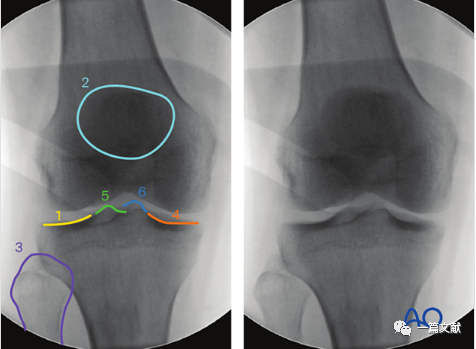

2)标准正位的评估:1、髌骨下极位于股骨双髁之间 2、腓骨头的1/4-1/3被胫骨外侧平台遮盖。如下图:

3)解剖标志的识别:如下图:1、外侧胫骨平台关节面 2、髌骨 3、腓骨头4、内侧胫骨平台5、外侧髁间脊6、内侧髁间脊。

4)标准正位的意义:1、评估关节内骨折块复位情况(关节面台阶)2、检视关节内的游离骨块或突入关节的内植物3、内翻或外翻应力下关节间隙变化情况(侧副韧带损伤指征)4、髁间脊撕脱骨折的评估(叉韧带损伤情况)5、评估胫骨关节线和胫骨轴线之间的角度(85-90°)。